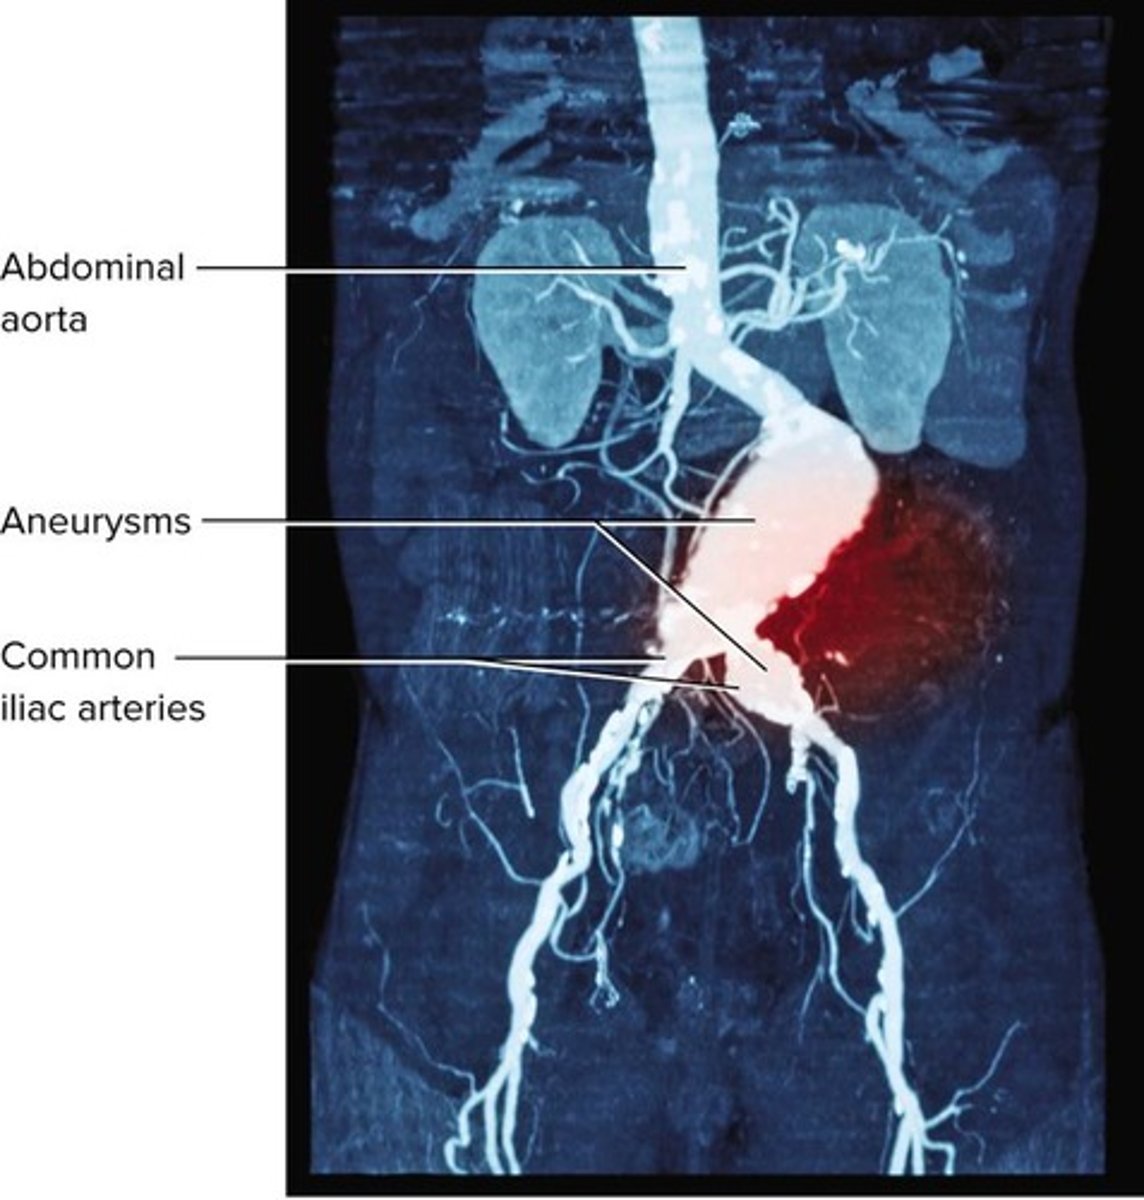

What is an aneurysm?

A weak point in an artery or heart wall that forms a bulging sac that may rupture.

Can weaken arteries, cause aneurysms, and promote atherosclerosis.